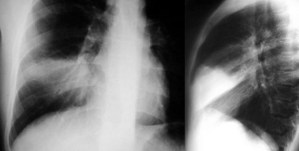

Cuando en una radiografía de tórax se ve un nivel hidraéreo hay que establecer la diferencia entre intrapulmonar (absceso, quiste, tumor cavitado) o extrapulmonar (derrame encapsulado, empiema). La ausencia de la pared superior de una colección intratorácica con nivel hidroaéreo, en al menos una de las dos proyecciones de tórax, es un signo que permite diferenciar el encapsulado pleural de cavidades de localización intrapulmonar.

En las imágenes vemos un nivel hidroaéreo en hemitórax derecho (flechas rojas) sin que sea visible la pared de la cavidad. Se trata por tanto de una colección extrapulmonar.

Estos esquemas permiten entender el significado del signo. Las colecciones intrapulmonares (izquierda) suelen tener una morfología redondeada, ya que están rodeadas por entero de pulmón y la resistencia de este al crecimiento de la colección es igual en todos sus puntos. Por ello, en las dos proyecciones los bordes superiores de la cavidad -delimitados por el aire que contiene la misma- son perpendiculares a la incidencia del rayo, y por tanto son visibles.

Las colecciones extrapulmonares (derecha) tienen a crecer limitadas por la pleura, que ofrece resistencia al crecimiento de la colección. Así, estas colecciones tienen una forma alargada (en «huso») a lo largo del espacio extrapulmonar. Por ello, en al menos una de las proyecciones, los bordes de la cavidad no son perperdiculares a la incidencia del rayo, y por tanto no son visibles. Como muestra el esquema, las colecciones posteriores (y también las anteriores, se ven bien en la proyección lateral y falta la pared superior en la proyección PA. Con las colecciones laterales ocurre lo contrario.